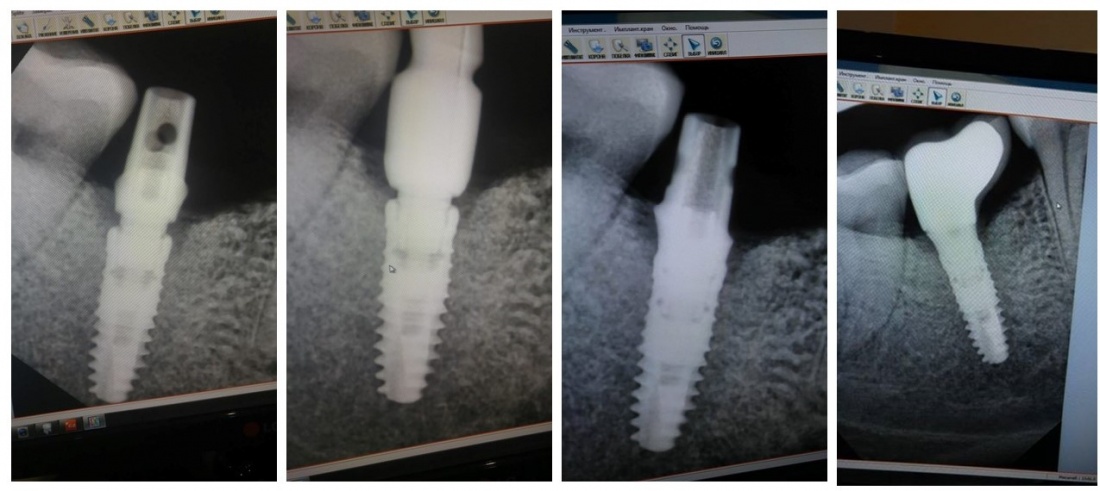

Мы сделали рентгеновские контрольные снимки —  панорамный для оценки положения имплантатов и прицельный для контроля посадки абатментов.

На последнем видно, что абатменты (особенно правого на фото зуба) не сели на свои места, между ними и платформами имплантатов есть щель — и эта ситуация наглядно демонстрирует, ПОЧЕМУ такие снимки необходимы. Мы вернули пациентку в хирургический кабинет и провели коррекцию абатмента (уменьшили ширину трансгингивальной части), После чего, проводили пациентку в кабинет стоматолога-ортопеда для временного протезирования.

После фиксации временных коронок мы делаем прицельный контрольный снимок для контроля посадки абатментов на платформу и оценки качества изготовления композитных реставраций.

затем сняли оттиски и передали из в зуботехническую лабораторию. Кстати, на этом этапе мы также рекомендуем делать прицельные снимки для контроля посадки трансферов.

Вот клиническая картина и рентгенологический контроль через 2,5 года после имплантации и протезирования:

Данные конусно-лучевой компьютерной томографии области имплантации через 2,5 года выглядят более интересными:

Как видите, под приемлемыми объёмами и состоянием десны в области имплантатов скрывается надёжный фундамент — восстановленная и сохраненная с помощью аугментации костная ткань, состояние которой за два с половиной года только улучшилось.